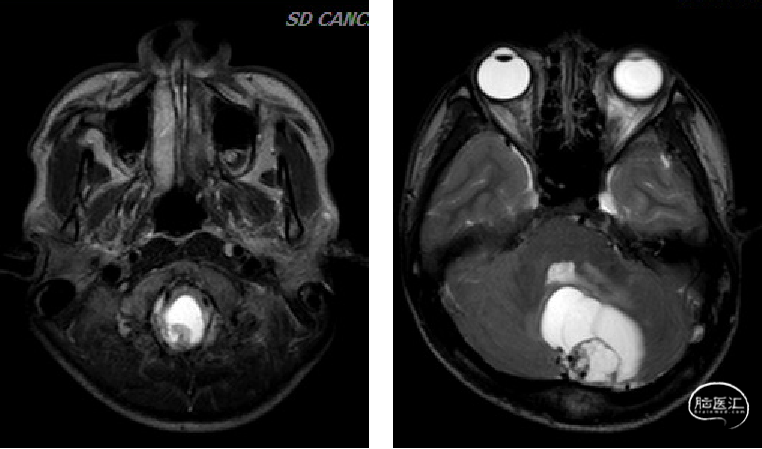

术前MRI

image.png

诊断及手术方式

术前诊断:

1.小脑、延髓占位(血管母细胞瘤)

2.梗阻性脑积水

手术方式:

枕下后正中入路延髓及小脑半球病损切除术